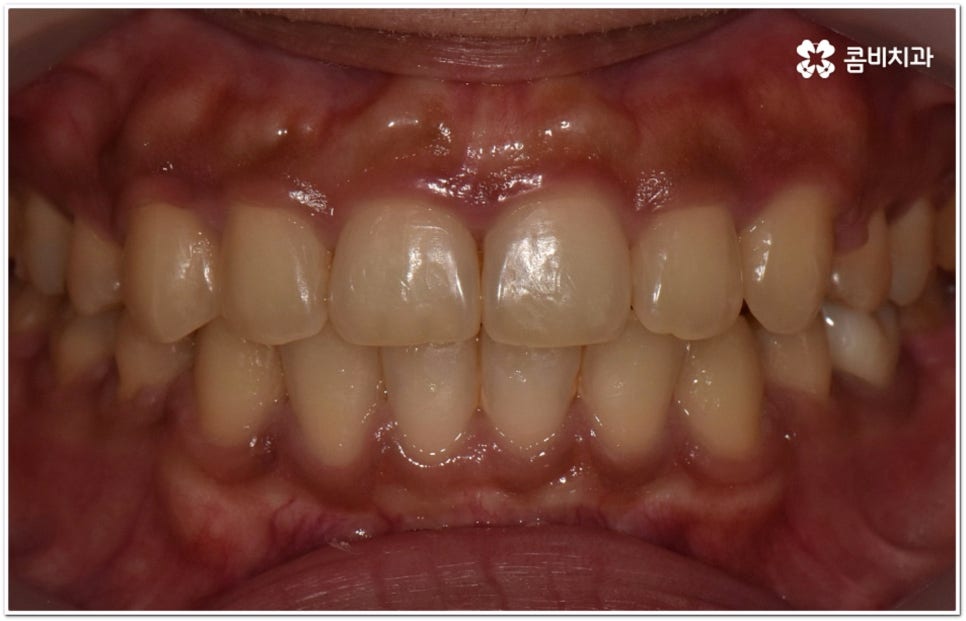

이때 위아래 치아가 맞물리는 데는 별다른 문제가 없고 앞니 등 치아가 조금 뻐드러진 상황이라면 각도만 개선해도 되지만 잇몸뼈 자체가 나와 있고 교합에도 문제가 있다면 종합적인 해결이 필요할 수 있는데요.

단순히 치아가 튀어나온 각도를 고친다고 돌출입 개선이 되지는 않고 구조적 골격적인 원인을 파악하여 해결해야 추후 턱관절 건강 부분에까지 좋지 않은 영향을 미치는 것을 막을 수 있습니다.

환자마다 치열, 교합, 치아가 튀어나온 각도, 잇몸이 드러나는 정도, 상악과 하악의 구조 및 관계 등 턱관절 관련 부분 상황이 모두 다르기 때문에 3D CT 같은 정밀 검진 기계를 통해 이를 꼼꼼하게 살펴보고 각각에 맞는 계획을 세밀하게 세워 교정 치료를 진행해 줄 필요가 있어요. 이때 환자분들의 상황에 따라 양악수술과 같은 외과적인 방법을 병행해야 하는 케이스도 있을 수 있기 때문에 돌출입을 가지고 계신 분들 중에서 수술에 부담을 느끼고 지레 치료를 포기하신 분들도 있을 수 있는데 정도가 많이 심각하지 않고 구조적인 원인이 크지 않다면 대부분의 케이스는 치아교정 만으로도 충분히 개선이 가능하니 먼저 돌출입교정치과 에 들러서 정밀 검사를 진행한 후 치료 방향에 대해 의료진과 논의해 보시면 좋을 거예요.